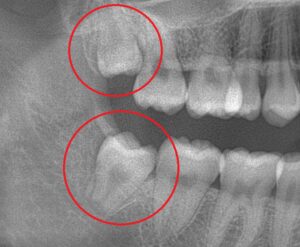

このようにスペースのない顎の中で斜めに生えていたり、骨の中で水平に埋まっていたりすると前の歯を押してしまい、歯並びが崩れてしまうこともあります。

さらに、親知らずが生えていると奥歯の清掃も困難になるため、虫歯のリスクもあります。歯並びへの影響や虫歯のなりやすさの観点からも、状況によっては親知らずの抜歯が推奨されることは少なくありません。

真っすぐに生えて、噛み合わせに問題がなければ無理に抜く必要はありませんが、親知らずが生えていなくても、その後の歯の微妙な動きによって影響が出てくる場合もあるため、定期的にレントゲン撮影で確認することが重要となります。

当院では資料取りの際や、矯正治療中に適宜レントゲン撮影を行っております。これにより、患者様の歯並びの状況や歯周組織の健康状態も確認しております。また、親知らずの有無や状態もこの際に確認し、患者様とお話しながら必要に応じて抜歯などの対策も一緒に検討していきます。